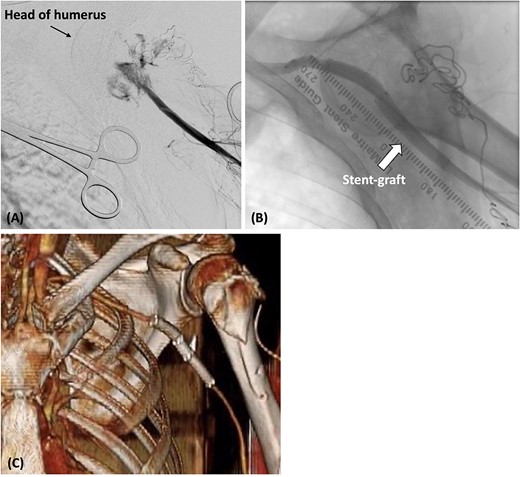

During open reduction, active arterial bleeding was identified from the incision site along with an absent left radial artery pulse. After consultation, we exposed the left brachial artery and inserted a 6-Fr sheath. Angiography revealed a rupture of the axillary artery (Fig. 2A). Because we were unable to penetrate the injured axillary artery with the guidewire from the brachial artery, we placed a 4-Fr catheter (Judkins Right4.0, MEDIKIT CO., Ltd., Tokyo, Japan) at the origin of the left subclavian artery from a right femoral approach. We then advanced a 0.014-inch guidewire (Jupiter FC Guide Wire, Boston Scientific, Marlborough, MA, USA) along a 1.9-Fr/2.5-Fr Fencer microcatheter to the left brachial artery. A 6-Fr snare catheter was inserted through the left brachial artery. The guidewire inserted from the right femoral artery was pulled through the left brachial artery. Intravascular ultrasonography was used to measure the inner diameter of the artery on the proximal and distal sides of the axillary artery injury site (7.7 mm on the proximal side and 6.5 mm on the distal side). Two Gore Viabahn stent grafts (7 × 50 mm and 8 × 50 mm; W. L. Gore and Associates Inc., Flagstaff, AZ, USA) were deployed retrogradely from the brachial artery (Fig. 2B). The stent grafts were expanded using an 8.0 × 60-mm balloon (SHIDEN HP: Kaneka Medical Products, Japan). Final angiography showed good blood flow inside the stent graft with no endoleaks. The reduction of the shoulder dislocation was then completed.

(A) The catheter was inserted from the left brachial artery, and angiography revealed the extravasation of the axillary artery. (B) Stent grafts were placed at the site of the axillary artery rupture to confirm that there was no leakage. (C) Postoperative contrast-enhanced CT revealed that blood flow in the axillary artery was maintained.